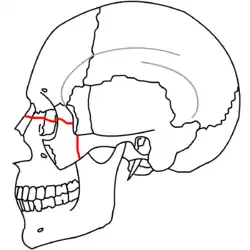

|

|

| Le Fort II fractures | |

|

|

| Le Fort III fractures | |

At the beginning of the 20th century, René Le Fort mapped typical locations for facial fractures; these are now known as Le Fort I, II, and III fractures (right).[7] Le Fort I fractures, also called Guérin or horizontal maxillary fractures,[14] involve the maxilla, separating it from the palate.[15] Le Fort II fractures, also called pyramidal fractures of the maxilla,[16] cross the nasal bones and the orbital rim.[15] Le Fort III fractures, also called craniofacial disjunction and transverse facial fractures,[17] cross the front of the maxilla and involve the lacrimal bone, the lamina papyracea, and the orbital floor, and often involve the ethmoid bone,[15] are the most serious.[18] Le Fort fractures, which account for 10–20% of facial fractures, are often associated with other serious injuries.[15] Le Fort made his classifications based on work with cadaver skulls, and the classification system has been criticized as imprecise and simplistic since most midface fractures involve a combination of Le Fort fractures.[15] Although most facial fractures do not follow the patterns described by Le Fort precisely, the system is still used to categorize injuries.[5]